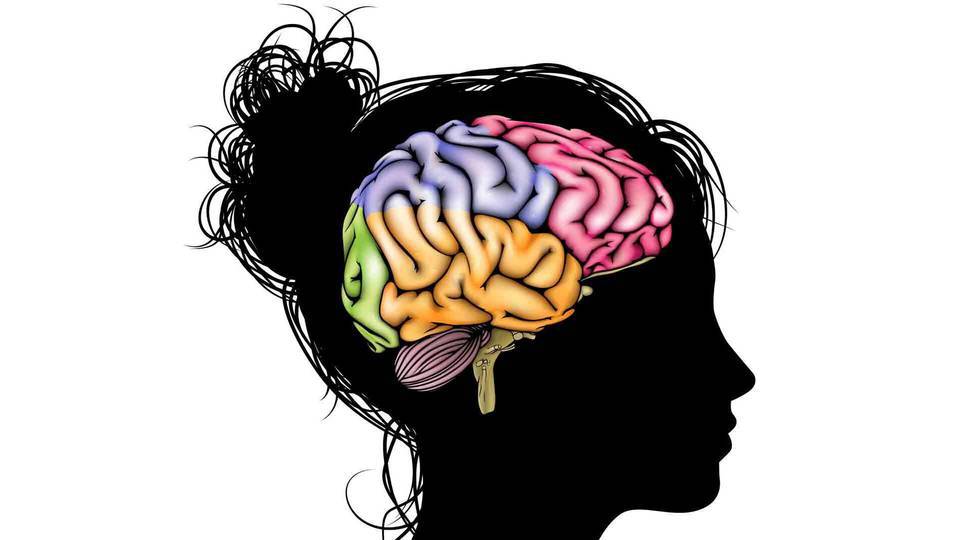

Frisss.hu/Yahoo.com - Fotó: kqed.org • 2017. február 03., péntek • 12:28

A mentális zavarainknak alakja is van...